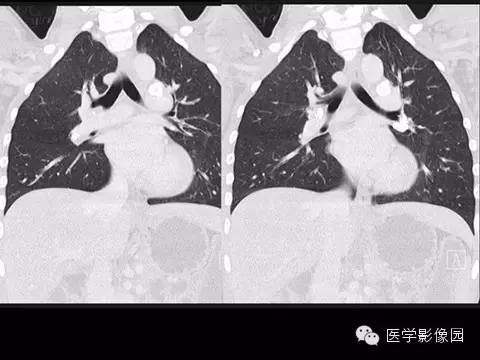

【病例】组织胞浆菌病1例CT影像表现

X线检查、CT:可见肺、肝、脾等脏器可有许多钙化点。纵隔组织胞浆菌病还包括纵隔的肉芽肿和纤维化性纵隔炎。组织胞浆菌病大多数不需要特殊治疗,通常经过卧床休息、加强营养等支持疗法后,多在3个月至数年间自然痊愈。